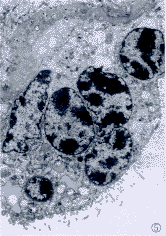

2.3.1 高原组胎盘绒毛的超微结构 (1)合体细胞增生(图5),合体结节增多,部分合体细胞的粗面内质网高度扩张,胞质内出现空泡,细胞器减少,核异染色质边集,核周间隙加大,表面微绒毛短而少。(2)细胞滋养细胞均有增生,其程度不等,增生明显者往往数个相连成串,并见双核细胞(图6);增生细胞中,多数细胞超微结构与正常相似,少数细胞可见粗面内质网扩张。(3)部分绒毛滋养叶基底层增厚,增厚程度不等,可达正常的几倍至十几倍(图7)。(4)毛细血管的改变,部分毛细血管的内皮细胞肿胀,管腔变狭窄,少数内皮细胞见粗面内质网扩张,线粒体肿胀,毛细血管增生,部分扩张充血,个别血管腔内有血栓形成。

图5 合体细胞结节,基底膜增厚,粗面内质网扩张。EM×4 000

图6 郎罕细胞增生,出现双核。EM×3 000

图7 郎罕细胞,粗面内质网扩张,基底腊增厚明显。EM郎罕细胞5 000